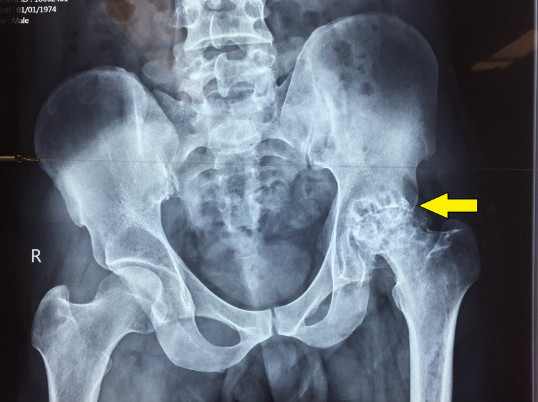

- X quang: Bao gồm phim chụp X quang khớp háng thẳng và nghiêng, xquang khớp háng kiểu đùi chếch là phương tiện đầu tiên được lựa chọn để chẩn đoán hoại tử chỏm xương đùi.

- Phim MRI (cộng hưởng từ): Khi hình ảnh trên phim x quang không rõ, hay chưa đủ để chẩn đoán chính xác bệnh thì cho chụp cộng hưởng từ MRI là phương tiện chẩn đoán sớm và chính xác hoại tử chỏm xương đùi.